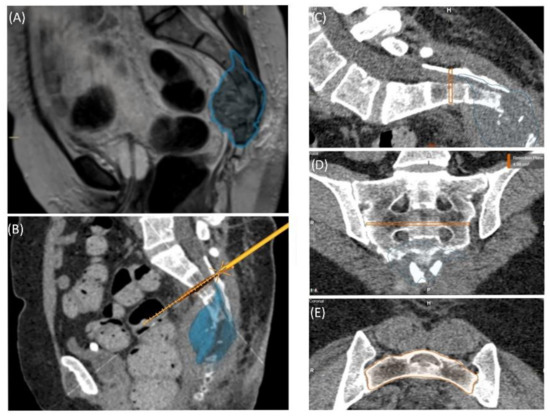

A 58-year-old male patient was diagnosed with a giant cell tumor of the left pelvis in 2013. After five years of conservative treatment with denosumab, he developed recurrent jawbone osteonecrosis. Therefore, the treatment was stopped in 2018. Consequently, tumor progression with increasing symptoms occurred, and surgical resection was indicated after rebiopsy and histopathological confirmation. Intralesional resection was performed via high-speed burr curettage followed by adjuvant polymethyl methacrylate filling (Figure 8 and Figure 9). This approach allowed preservation of the hip joint. Foot drop on the left side was noted postoperatively, and hip flexion was restricted to 60° for 4 weeks postoperatively to avoid luxation. At the 6-month follow-up, the patient had free range of motion of the hip in all directions except for a maximum of 10° external rotation. The foot drop increasingly improved, and orthosis was no longer necessary at this point.

Figure 8. Case 5: Segmentation of the giant cell tumor in magnetic resonance imagining (MRI) (A) and computed tomography (CT) (B) scans, segmented tumor volume (C), high-speed burr navigation (D), intraoperative navigation of the tumor volume with the high-speed burr tool tip (E,F).

Figure 9. Case 5: Preoperative plain radiograph of the acetabular giant cell tumor (A) and postoperative result after resection of the dorsal parts and intralesional curettage with a navigated burr and augmentation with polymethyl methacrylate (B).